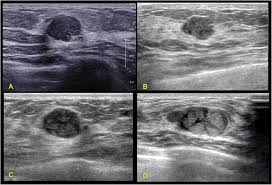

This breast cancer ultrasound image shows changes related to breast cancer that are not seen as microcalcifications or a mass or lump.

The age of the patient, large size of tumor and typical ultrasound features are highly suggestive of this being a phyllodes tumor of the left breast. During a breast exam, your doctor looks for visual changes and uses their fingers to feel. A mammogram image has a black background and shows the breast in variations of gray and white. Below are images of dcis on breast ultrasound. There is a slight increase in the density in the right breast compared with the left. You might get an mri. Breast infections can cause redness and swelling. Palpation of benign breast masses. Finding breast lumps and seeing change in the size and shape. This breast cancer ultrasound image shows changes related to breast cancer that are not seen as microcalcifications or a mass or lump. Any area that does not look like normal tissue is a possible cause for concern. Epidemiology these account for ~1% of breast cancers. If you have calcifications, they'll show up as white spots.

As the machine is moved over an area of the breast, the device sends sound waves into the tissue, and it shows an image based on how quickly those waves bounce back to it. Ultrasound does not use or. The lump may shows a combination of clustered tiny cysts and thickened parenchyma (arrows in c) Ultrasound may be particularly useful in detecting abnormalities in patients with dense breasts. Presenting radiologic appearance of breast dcis microcalcifications at breast cancer screening we can see from the chart above that overall, the most commonly occuring mammographic indication of dcis are the crushed stone microcalcifications.